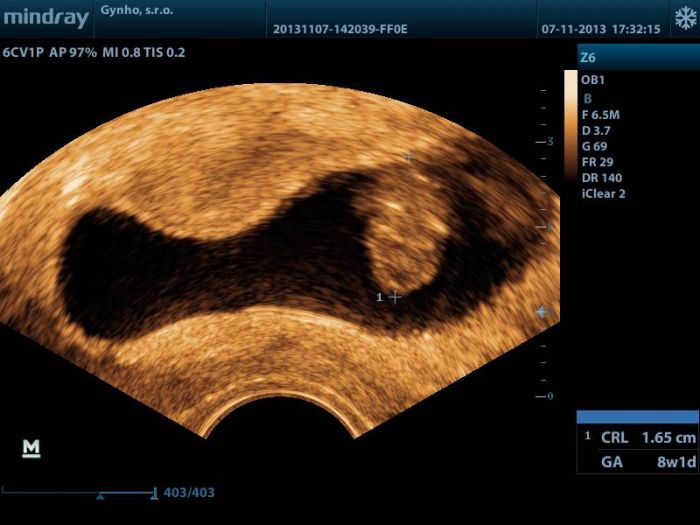

[386075] Kásná fotečka :) taky hodím svoji z dneška, ale nic moc kvalita :(

Jinak tady je fotečka mojí bublinky...jméno máme pro chlapečka František ( táta, jeho tátá, můj tátá a můj děda jsou taky všichni tři Františkové) a pro holčičku, kterou si moc přeju chci jméno Nina :)

[386089] téda, vždyť ji máš krásnou!! i ty barvy... a pochopila jsem správně, že máš 1,65 cm ? tak to mám skoro i já.. máme 1,62 cm. V jakém jsi týdnu? Mě Dr. řekla, že jak jsem měla nepravidelnou MS, tak se to pozná až déle. Gratuluji, krásná bublinka..

takže jsem v 8+5, ale podle velikosti 8+1 :) a asi to chápu taky ty centimetry jako ty na té fotce...ja nevím jestli s emi to nezdá, ale vypadá to, že bublinka je jakoby seshora vyfocena a má tam někde ručičky...zhruba v prostředku taková plotvička...ale asi to tam vidět chci, tak to tam vidím